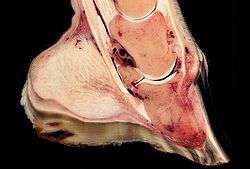

The bones of the hoof are suspended within the axial hooves of ungulates by layers of modified skin cells, known as laminae or lamellae, which act as shock absorbers during locomotion. In horses, there are about 550–600 pairs of primary epidermal laminae, each with 150–200 secondary laminae projection from their surface.[1] These interdigitate with equivalent structures on the surface of the coffin bone (PIII, P3, the third phalanx, pedal bone, or distal phalanx), known as dermal laminae.[2] The secondary laminae contain basal cells which attach via hemidesmosomes to the basement membrane. The basement membrane is then attached to the coffin bone via the connective tissue of the dermis.[1]

Laminitis literally means inflammation of the laminae, and while it remains controversial whether this is the primary mechanism of disease, evidence of inflammation occurs very early in some instances of the disease.[3] A severe inflammatory event is thought to damage the basal epithelial cells, resulting in dysfunction of the hemidesmosomes and subsequent reduction in adherence between the epithelial cells and the basement membrane.[4] Normal forces placed on the hoof are then strong enough to tear the remaining laminae, resulting in a failure of the interdigitation of the epidermal and dermal laminae between the hoof wall and the coffin bone. When severe enough, this results in displacement of the coffin bone within the hoof capsule.[4] Most cases of laminitis occur in both front feet, but laminitis may be seen in all four feet, both hind feet, or in cases of support limb laminitis, in a single foot.[4]

Rotation, sinking, and founder

Normally, the front of the third phalanx is parallel to the hoof wall and its lower surface should be roughly parallel to the ground surface. A single severe laminitic episode or repeated, less severe episodes can, depending upon the degree of separation of dermal and epidermal laminae, lead to either rotation or sinking of the pedal bone, both of which result in anatomical changes in the position of the coffin bone with visible separation of the laminae, colloquially known as founder. Rotation and distal displacement may occur in the same horse.[4] Both forms of displacement may lead to the coffin bone penetrating the sole. Penetration of the sole is not inherently fatal; many horses have been returned to service by aggressive treatment by a veterinarian and farrier, but the treatment is time-consuming, difficult and expensive.

Rotation is the most common form of displacement, and, in this case, the tip of the coffin bone rotates downward.[4] The degree of rotation may be influenced by the severity of the initial attack and the time of initiation and aggressiveness of treatment. A combination of forces (e.g. the tension of the deep digital flexor tendon and the weight of the horse) result in the deep digital flexor tendon literally pulling the dorsal face of the coffin bone away from the inside of the hoof wall, which allows the coffin bone to rotate. Also, ligaments attaching the collateral cartilages to the digit, primarily in the palmar portion of the foot, possibly contribute to a difference in support from front to back. The body weight of the animal probably contributes to rotation of the coffin bone. Rotation results in an obvious misalignment between PII (the short pastern bone) and PIII (the coffin bone). If rotation of the third phalanx continues, its tip can eventually penetrate the sole of the foot.

Sinking is less common and much more severe. It results when a significant failure of the interdigitation between the sensitive and insensitive laminae around a significant portion of the hoof occurs. The destruction of the sensitive laminae results in the hoof wall becoming separated from the rest of the hoof, so that it drops within the hoof capsule. Sinking may be symmetrical, i.e., the entire bone moves distally, or asymmetric, where the lateral or medial aspect of the bone displaces distally.[4] Pus may leak out at the white line or at the coronary band. In extreme cases, this event allows the tip to eventually penetrate the sole of the foot. A severe "sinker" usually warrants the gravest prognosis and may, depending upon many factors, including the quality of aftercare, age of the horse, diet and nutrition, skill, and knowledge and ability of the attending veterinarian and farrier(s), lead to euthanasia of the patient.